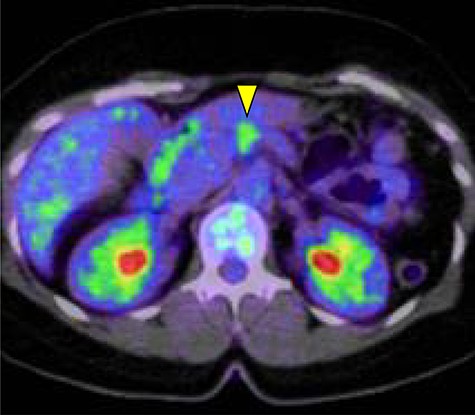

Abdominal-enhanced computed tomography (CT) revealed a low-density pancreatic body tumor of 25 mm in diameter, which was close to the gastroduodenal artery (GDA), and was accompanied by atrophy of the distal pancreatic parenchyma and dilation of the upstream MPD (Fig. 1A). Moreover, CT imaging of the portal phase revealed a filling defect within the splenic vein where it was in contact with the tumor (Fig. 1B). On magnetic resonance imaging, the tumor appeared as an area of signal hyperintensity on T2-weighted and diffusion-weighted images (Fig. 2A and B). On positron emission tomography-CT scan, the tumor exhibited greater uptake of 18F-fluorodeoxyglucose (Fig. 3). Although a definitive preoperative diagnosis could not be made, we suspected pancreatic ductal adenocarcinoma, and distal pancreatectomy with lymph node dissection was scheduled, without neoadjuvant chemotherapy, after obtaining consent from the patient. The pancreas was divided along the left edge of the GDA after mobilization of the artery; however, pathological examination of a frozen section of the pancreas stump was positive for PNET, and therefore a total pancreatectomy was performed (Fig. 4). The duration of surgery was 610 min, the intraoperative blood loss was 195 mL, and blood transfusion was not performed.

The pancreatic tumor exhibited greater uptake of 18F-fluorodeoxyglucose (standardized uptake value of 3.8) on positron emission tomography (yellow arrow).